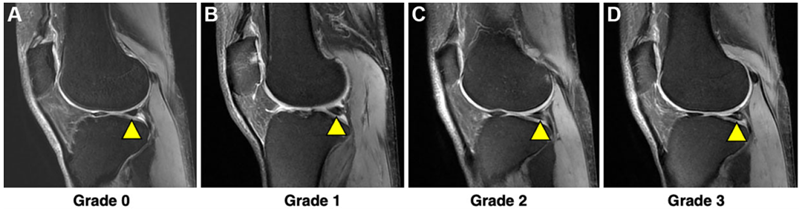

半月板病变的MRI分级系统如下:

0级:半月板完整,表现为均匀一致的低信号;

Ⅰ级:局灶性小范围高信号,不延伸至半月板表面;

Ⅱ级:线状高信号区,可延伸至半月板关节囊缘;

Ⅲ级:至少累及1个关节面的异常高信号,提示明确的半月板撕裂。

MRI分级,A:0级信号,正常外侧半月板(箭头所示)无退行性改变或撕裂,T2加权MRI显示半月板内无信号。B:Ⅰ级信号,MRI上缘不规则信号(箭头),信号不与上、下关节半月板面相通。但在关节镜下,外侧半月板后角是正常的。C:Ⅱ级板信号,MRI上以线状信号(箭头)为主。D: Ⅲ级信号,半月板(箭头)内的主要线性信号强度,信号紧贴关节面